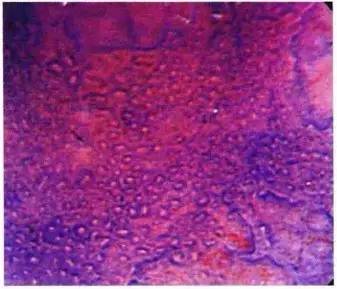

图4b:II型pit:星芒状pit。

粘膜组织增生后,病理学上pit pattern会形成锯齿状改变,从水平断面观察可看到类似星星一样的星芒状。

图4c:IIIL型pit:管状pit。

形成肿瘤性病变以后,上皮出现腺管与腺管融合性改变,可以回看图3d,理解为3个腺管融合为1个,形成了纵行的开口,表面观察成管状。